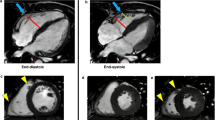

The Look-Locker technique involved VCG gating and a single breath hold technique. Approximately 20 images, each with a consecutively longer inversion time, were acquired at the mid-ventricular level. Offline, regions of interest (ROI) were manually traced on each short axis image. These ROI were specifically placed within the mid RV free wall (orange), RV blood pool (aqua), mid RV septum (yellow) and mid LV lateral wall (blue) using prototype CVI42 software. When tracing the myocardial ROI, care was taken to avoid regions of LGE, non-myocardial structures, trabeculations and adjacent blood pool (Fig. 1).

Regional post-contrast T1 values were determined offline by manually tracing regions of interest (ROI) on the short axis cardiac magnetic resonance images at the mid ventricular level. These ROIs were specifically placed within the mid RV free wall (orange), RV blood pool (aqua), mid RV septum (yellow) and mid LV lateral wall (blue) using prototype analysis software